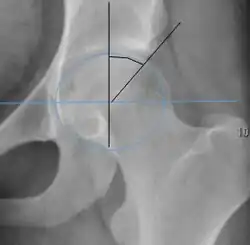

| Tönnis angle |

|

Slope of the sourcil (the sclerotic weight-bearing portion of the acetabulum) | 0 to 10°

|

| Caput-sourcil angle[12] |

|

Superior to the Tönnis angle in cases without joint space narrowing or subluxation.[12] The medial point of the sourcil is defined as being at the same height as the most superior point of caput femoris. | −6 to 12°[12]

|